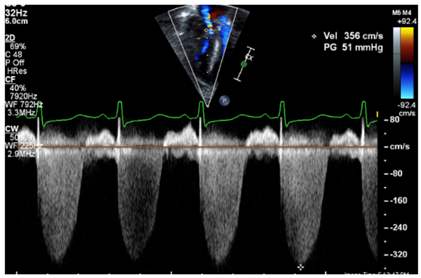

| RVSP estimation by tricuspid regurgitant jet velocity | Concern of PH if the RVSP > 40 mmHg by the TR jet (TR jet with an RV–RA gradient of >35 mmHg, assuming an RA pressure of 5 mmHg). RVSP > 1/2 of systemic pressure is concerning for abnormal pulmonary pressure. About 60% of echocardiograms may have a quantifiable TR jet with a full envelope. Some use the cutoff of the TR jet > 33.6 mmHg) [12,22]. |

| Tricuspid regurgitation jet | ![]() |

| Legend: The tricuspid regurgitant jet velocity provides information on the velocity of flow during systole from the RV to the RA. This allows to estimate, using the Bernoulli equation, the pressure gradient between the RV and the RA. A full envelope is generated when the line of interrogation is parallel to the tricuspid regurgitant jet. With an estimated RA pressure (typically 0–5 mmHg in a normal setting, but likely further increased in RV diastolic impairment), one is able to estimate the peak systolic RV pressure. Assuming that the RV and pulmonary arterial pressure are equalized at the peak of systole, one may infer the peak systolic pulmonary arterial pressure. The velocity measurement should be performed along the contour of the spectral Doppler envelope, avoiding overestimation of the measurement. In this case, the peak systolic RV–RA gradient has a velocity of 3.56 m/s, providing an estimated RV–RA pressure gradient of 51 mmHg (4 × 3.562). With an RA pressure of 5 mmHg, this provides a peak systolic RV pressure estimated at 56 mmHg (abnormal > 40 mmHg). | |